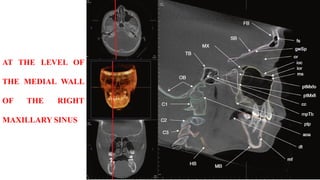

AT THE LEVEL OF

THE MEDIAL WALL

OF THE RIGHT

MAXILLARY SINUS